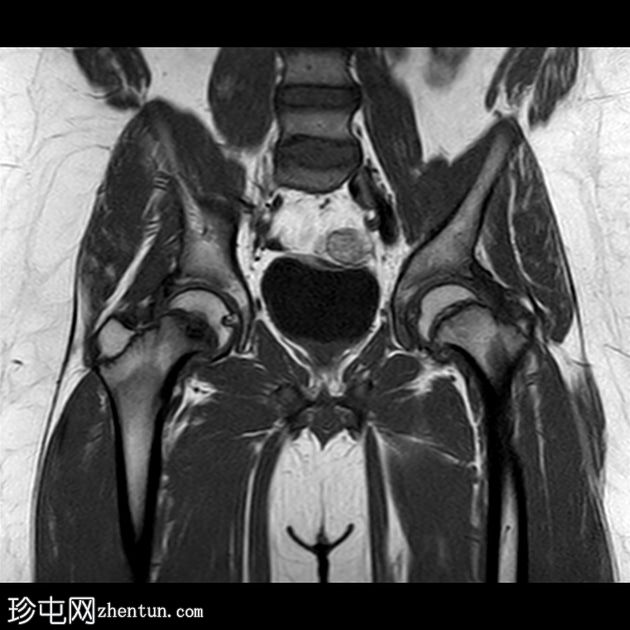

2.jpg

蛙式位片

双侧股骨近端骨骺皮质不规则,轻度增宽。

双侧股骨骨骺轻度后内侧移位。